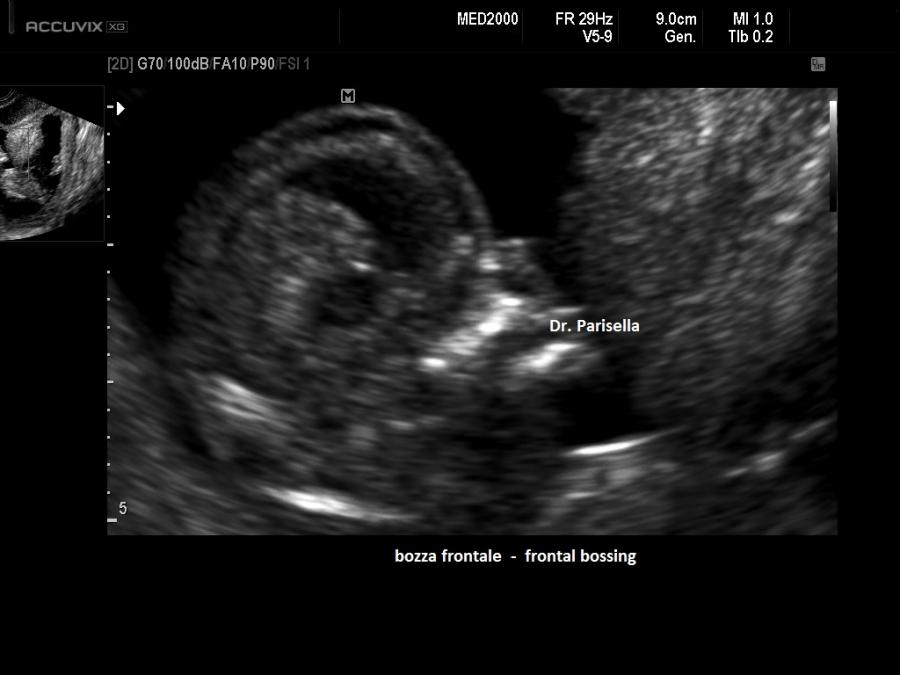

• dismorfismi cranio facciali: bozze frontali prominenti, radice del naso larga, facies appiattita